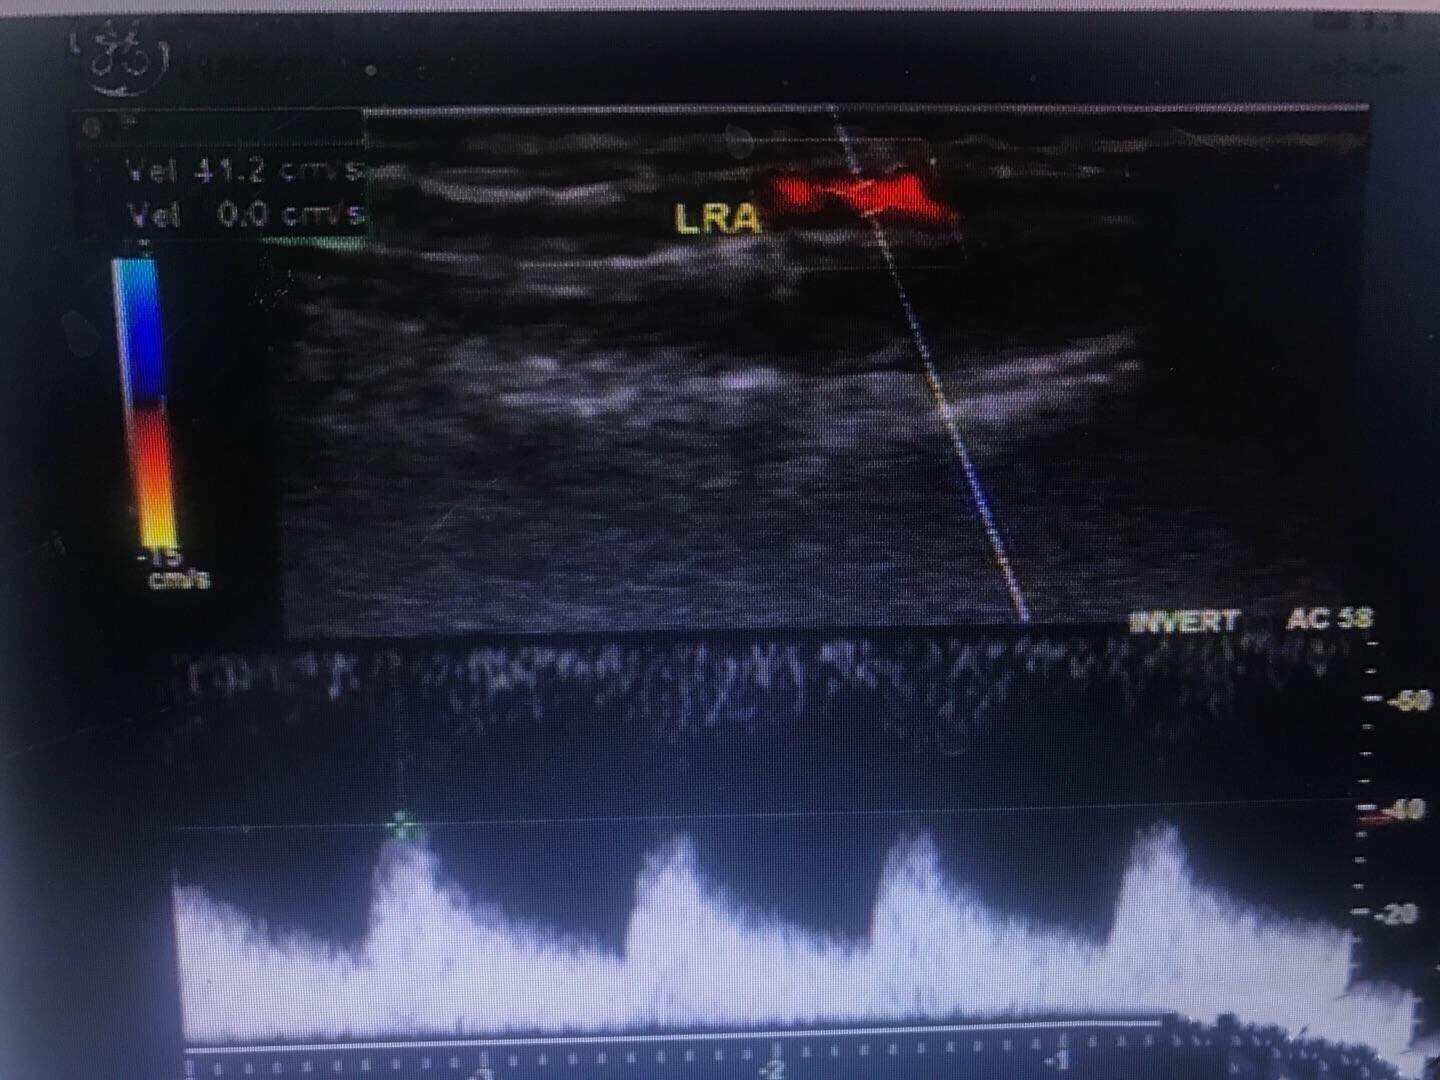

左侧桡动脉血流频谱,为低阻单相波形。左侧椎动脉和左侧颈总动脉血流,二者血流方向相反。 右侧和左侧锁骨下动脉起始部,左侧明显较右侧管径细。